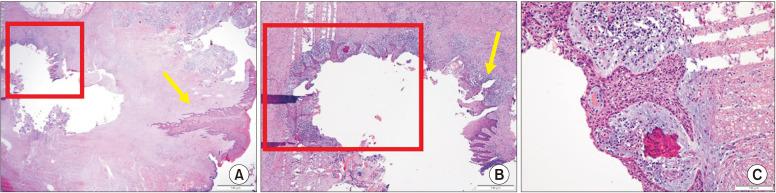

Primary intraosseous squamous cell carcinoma (PIOSCC) is very rare type of squamous cell carcinoma (SCC) that occurs within the jaw and arises from remnants of odontogenic epithelium with no connection to the oral mucosa. This study reports two cases of PIOSCC of the mandible. Reported in this article are two cases of PIOSCC of the mandible that were treated with resection and reconstruction using a fibular free flap. The first case was a 36-year-old male patient who complained of right mandibular pain. Computed tomography (CT) and panoramic radiograph revealed a large radiolucency in the mandibular ramus area. At first, an odontogenic keratocyst was tentatively diagnosed, and an excision procedure was carried out at another clinic. A final biopsy after cyst enucleation revealed well-differentiated SCC, so we proceeded with segmental mandibulectomy and reconstruction using a fibular free flap. The second case was a 48-year-old male patient with left mandibular pain. CT and panoramic radiograph revealed irregular radiolucency in the mandibular angle area near tooth #38. At first, osteomyelitis was tentatively diagnosed, and a curettage was carried out. A later biopsy revealed well-differentiated SCC, so segmental mandibulectomy and reconstruction with a fibular free flap were secondarily performed. Our two cases have had no recurrence. The facial appearance of both patients is satisfactory, and the neo-mandibular body created using a fibular bone transfer displays adequate bony volume.

原发性骨内鳞状细胞癌(PIOSCC)是一种非常罕见的鳞状细胞癌(SCC),发生于颌骨内,起源于牙源性上皮残余,与口腔黏膜无连接。本研究报告了两例下颌骨PIOSCC病例。本文报道了两例下颌骨PIOSCC病例,采用游离腓骨瓣进行切除和重建治疗。第一例是一名36岁男性患者,主诉右下颌疼痛。计算机断层扫描(CT)和全景X线片显示下颌支区域有一个大的透射区。起初,初步诊断为牙源性角化囊肿,并在另一家诊所进行了切除手术。囊肿摘除后的最终活检显示为高分化SCC,因此我们进行了下颌骨节段性切除并用游离腓骨瓣进行重建。第二例是一名48岁男性患者,有左下颌疼痛。CT和全景X线片显示38号牙附近下颌角区域有不规则透射区。起初,初步诊断为骨髓炎,并进行了刮除术。后来的活检显示为高分化SCC,因此二期进行了下颌骨节段性切除并用游离腓骨瓣进行重建。我们的两例病例均无复发。两名患者的面部外观均令人满意,使用腓骨骨移植构建的新下颌体显示出足够的骨量。